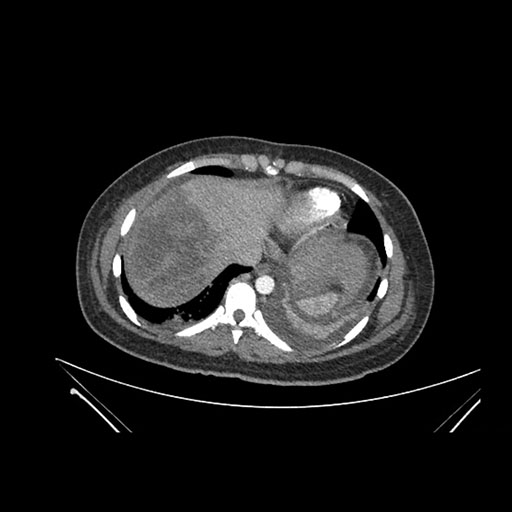

Axial Arterial

Imaging analysis

Based on initial findings, which issue(s) would you be most concerned about?